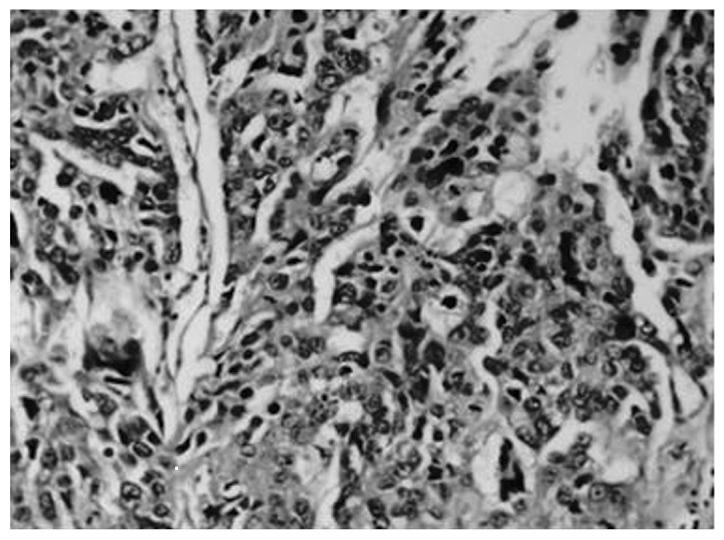

The present report investigated the correlation between the expression levels of matrix metalloproteinase (MMP)-9 in gastric carcinoma patients and the clinicopathological characteristics. Forty-five samples of gastric carcinoma and distal gastric mucosa tissue, and 10 samples of healthy gastric mucosa tissue were analyzed using semi-quantitative polymerase chain reaction, as well as immunohistochemical and hematoxylin and eosin staining. MMP-9 protein levels in serum samples from the same patients were quantified by enzyme-linked immunosorbent assay. The present report identified that MMP-9 expression was markedly higher in the gastric carcinoma tissue (86.67%) than in the adjacent healthy tissue (10.00%). A positive association was identified between the level of MMP-9 protein expression and the depth of cancer invasion (P<0.05). Furthermore, the preoperative serum levels of the MMP-9 protein in the gastric carcinoma tissue were correlated with the tumor-node-metastasis stage and occurrence of lymph node metastasis (P<0.01). Data from the present report indicates that MMP-9 may be key in gastric carcinoma malignancy, and implies that MMP-9 may serve as a novel biomarker in the diagnosis and prognosis of gastric carcinoma.

本报告研究了胃癌患者基质金属蛋白酶(MMP)-9表达水平与临床病理特征之间的相关性。采用半定量聚合酶链反应、免疫组织化学及苏木精-伊红染色法,对45份胃癌及远端胃黏膜组织样本和10份健康胃黏膜组织样本进行了分析。通过酶联免疫吸附测定法定量检测同一患者血清样本中MMP-9蛋白水平。本报告发现,MMP-9在胃癌组织中的表达(86.67%)明显高于相邻健康组织(10.00%)。MMP-9蛋白表达水平与癌症浸润深度呈正相关(P<0.05)。此外,胃癌组织中MMP-9蛋白的术前血清水平与肿瘤-淋巴结-转移分期及淋巴结转移的发生相关(P<0.01)。本报告的数据表明,MMP-9可能在胃癌恶性肿瘤中起关键作用,这意味着MMP-9可能作为胃癌诊断和预后的一种新型生物标志物。